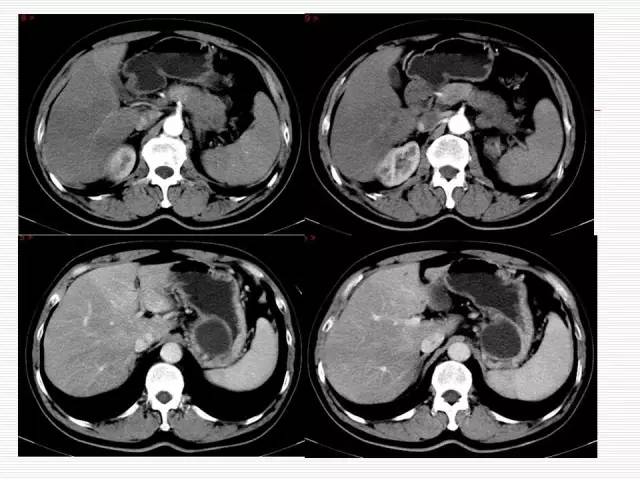

Case 2

Case 3

Case2: 胰腺真性囊肿

Case3: 胰腺癌伴潴留囊肿

潴留囊肿:为胰腺导管近端梗阻,远端扩张形成,因此囊肿与胰导管相通,多由近端肿瘤或结石引起。

真性囊肿:少见,为胰腺导管发育异常所致,内衬完整的内皮,为扁平或低柱状上皮。

单发或多发,囊腔不与胰管相通,囊内无间隔及软组织结节,可以单纯发生在胰腺,也可同时伴有肝肾的多囊病或VHL病(Von Hippel-Linda Disease),最终确诊要依靠病理。

胰腺癌囊性变:多由肿瘤组织阻塞导管引起潴留性囊肿或由肿瘤发生坏死液化而形成囊腔。

潴留性囊肿的近端常有实性肿块,肿瘤坏死囊变,肿瘤实性组织构成囊壁,故囊壁不完整,厚而不规则,或无明确囊壁显示。